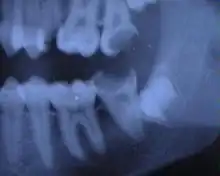

Cette infection peut être chronique : granulome péri-apical chronique ou kyste (ou desmodontite apicale chronique). L'infection évolue alors souvent à bas bruit pendant plusieurs mois voire plusieurs années, et n'est parfois détectée que par un contrôle radiographique de routine. Cette infection peut aussi être aiguë : abcès péri-apical aigu (ou desmodontite apicale aiguë). Voir : Endodontie.

Les dentistes utilisent désormais un détecteur de densité pour mesurer l'ampleur d'une déminéralisation de la dent, cela permet d'éviter une irradiation pour effectuer une radiographie.

Le dépistage de petites lésions dispose de trois techniques d’examen complémentaires à l'œil du dentiste : radio numérique en 2D, aides optiques de grossissement (loupes ou microscope opératoire), caméra vidéo numérique de fluorescence ou de transillumination [33].